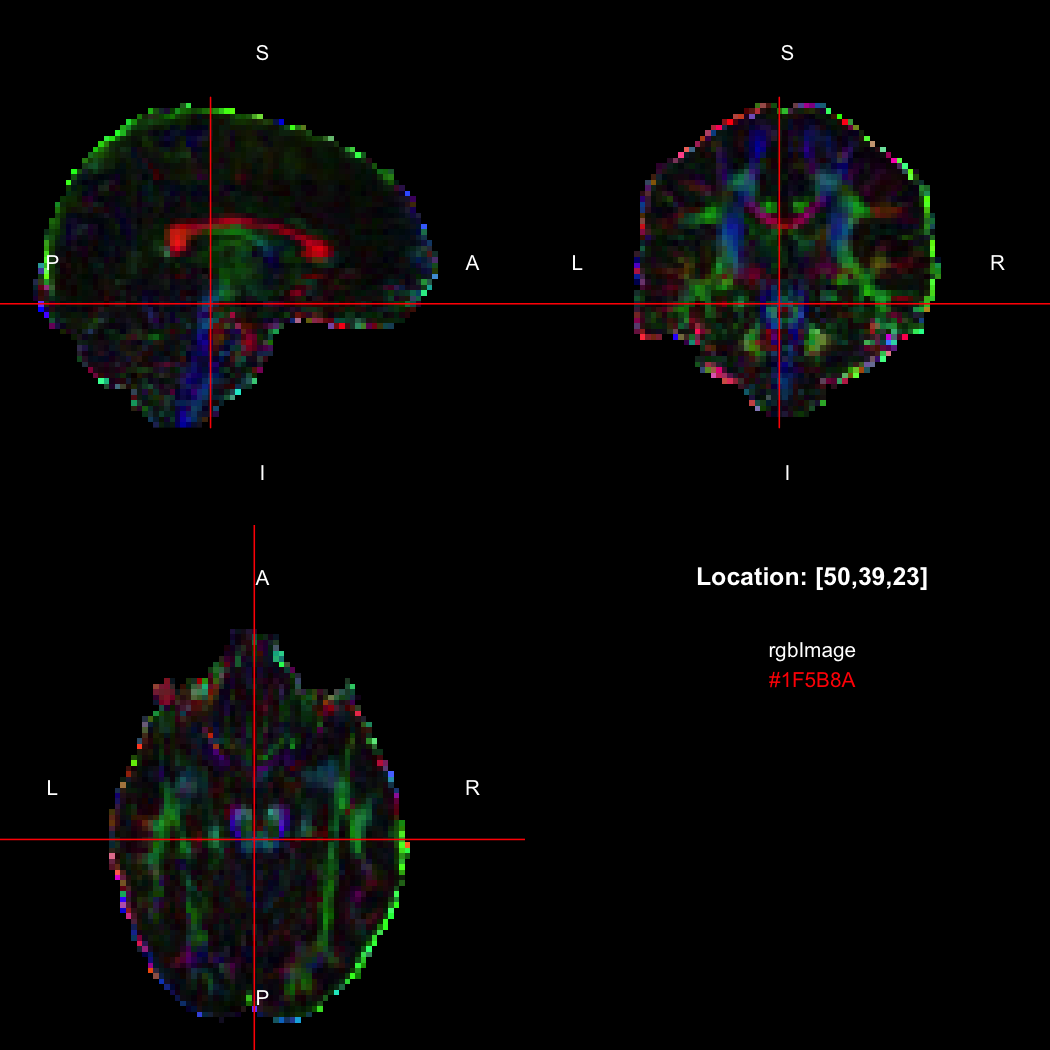

## [1] 300+0iR’s native representation for RGB values is CSS-style hex

strings of character mode, which are reasonably space-efficient (8

or 10 bytes per value) but a little clunky to work with. For efficiency

of interchange between R and the NIfTI-internal datatypes,

RNifti uses a byte-packed representation of integer mode

instead, which takes up 4 bytes per value. Of course, the viewer

understands this format.

rgbImage <- readNifti(system.file("extdata", "example_rgb.nii.gz", package="RNifti"))

print(rgbImage)

## Image array of mode "integer" (2.1 Mb)

## - 96 x 96 x 60 voxels

## - 2.5 x 2.5 x 2.5 mm per voxel

class(rgbImage)

## [1] "niftiImage" "rgbArray" "array"

view(rgbImage)

Notice that values are shown in the viewer using R’s conventional hex

string format, but the data is of class rgbArray. The

function of the same name can be used to create these arrays from

strings or channel values, for the purposes of building RGB images from

data, while the as.character method and

channels function perform the opposite conversions.

as.character(rgbImage, flatten=FALSE)[50,39,23]

## [1] "#1F5B8A"

channels(rgbImage, "red")[50,39,23,1]

## red

## 31RGB images with an alpha (opacity) channel are also supported.